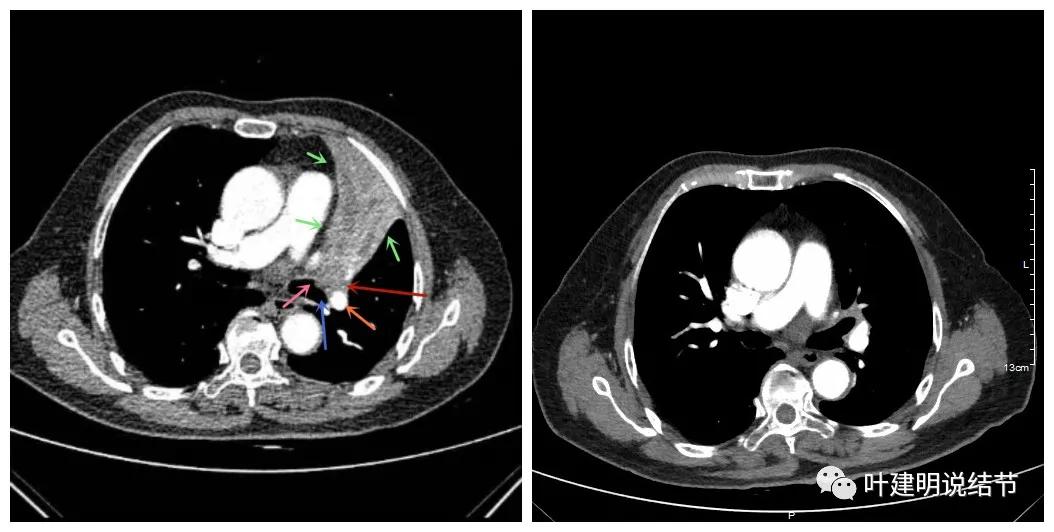

可见效果相当的好,如果我们把差不多同样层面的放到一起对比,更能显示化疗加免疫的惊人效果:

我样的治疗效果,显然超出了我们之前的预期,那么接下来拟选择行手术治疗,初定左上叶袖式肺叶切除加淋巴结清扫,但因为肺门区仍有软组织影,与肺动脉的关系仍密切,肿瘤与肺动脉间能否游离开来还是未知数,但至少得努力争取,鉴于患者年纪虽大,肺功能指标尚可,血气分析也基本正常,所以与患方沟通后确定行手术探查,但也也说明有万一全肺切除的可能(虽然这种可能性较小)。